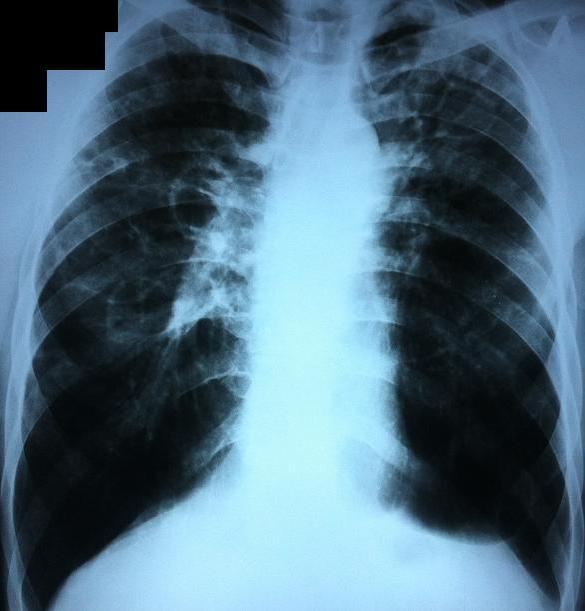

Рентгеновские снимки при врожденной эмфиземе легкого

Раздел: Визуальные уроки